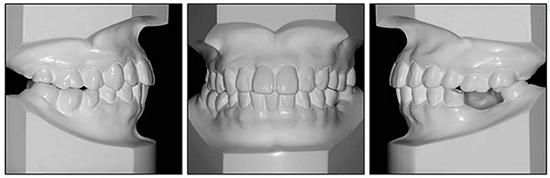

36歲;女性;尋求下頜左后方區(qū)域間隙管理的建議(圖1和圖2),通過治療獲得了良好的牙頜面效果(圖3和圖4)。她被診斷患有骨性I類和代償性牙性II類錯合畸形,并且上頜左側(cè)尖牙缺失(圖1和2)。大約七年前,由于不可修復(fù)的齲齒,拔除了下頜左側(cè)第一和第二磨牙(圖5)。37相鄰的第三磨牙向近中移動并傾斜入間隙,導致無牙頜間隙減小至約14 mm(圖2和圖5)。臨床和影像學評估顯示多發(fā)性齲損和在下頜右側(cè)567處有一不良的固定橋修復(fù)體(圖1和5)。此外,下頜左中切牙缺失,造成下頜中線向左側(cè)偏移約3 mm(圖1和圖2)?;颊咦栽V,她的右上第一前磨牙和左上尖牙在13歲時由其家庭牙醫(yī)拔除,因為它們被阻塞到頰側(cè)萌出(圖1)。上頜第二磨牙缺失(未知病因),并且相鄰的第三磨牙已經(jīng)轉(zhuǎn)移到第二磨牙間隙中。如補充材料所示,美國正畸學差異指數(shù)DI是28分。種植體部位(下頜左側(cè)和右側(cè)第一磨牙)由于復(fù)雜性得到額外4分(補充材料)。

圖1. 治療前面部和口內(nèi)照片

圖2. 治療前牙齒模型